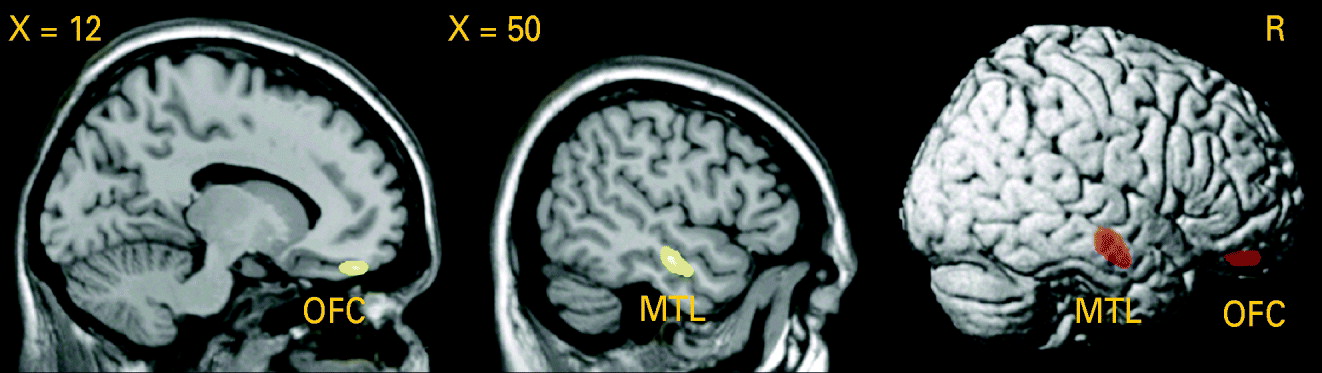

Testing the difference in GM volume between patients and healthy controls, we detected a significant GM volume reduction in the right middle temporal gyrus [Brodmann area (BA) 21: x=50, y=−15, z=−16, p (voxel-level)<0.001, k=1.56 cm3, p (cluster-level corrected)=0.01] in patients with PD, as shown in Fig. 3. Lowering the cluster-level threshold to the number of expected voxels per cluster, we detected an additional GM volume reduction in the medial part of the orbitofrontal cortex [BA 11: x=14, y=45, z=−20, p (voxel-level)<0.001, k=0.43 cm3, p (cluster-level corrected)=0.22; see Fig. 3). We did not observe any significant differences in the AHC and in the opposite contrast.

Fig. 3. Analysis using voxel-based morphometry (VBM): reduction of grey matter (GM) volume in patients with panic disorder (PD) relative to healthy controls (HC), voxel-level threshold: p<0.001 (uncorrected). Middle temporal lobe (MTL): p [cluster-level family-wise error (FWE) corrected]=0.01. Orbitofrontal cortex (OFC): cluster-level corrected according to the expected voxels per cluster.

When correlating the first eigenvariate (main component of the principal component analysis) extracted from the clusters of the significant GM difference in the middle temporal lobe and in the orbitofrontal cortex and the age at onset or duration of illness in patients with PD, there was a significant negative association between GM volume in the orbitofrontal cortex and the age at onset (r=−0.054, p=0.02).

The major findings of this quantitative volumetric and voxel-based morphometric MRI study were: a bilateral decrease in temporal lobe volume and a decrease in right frontal lobe volume in patients with PD. By means of VBM we were able to assess the abnormalities more precisely and detected significant GM volume reductions in the right middle temporal gyrus (BA 21) and in the medial part of the orbitofrontal cortex (BA 11).

In this study VBM analysis revealed a significant GM volume reduction in the right middle temporal gyrus and enabled the quantitative volumetric findings to be localized more precisely. Normal VBM results on the opposite side may indicate that abnormalities in the left temporal lobe are less pronounced or less specific. This point of view is also supported by the quantitative volumetric data: a volume decrease of the temporal lobe had a higher level of statistical significance on the right side (p<0.001) compared to the left (p<0.03). When comparing quantitative volumetry and VBM, it should be taken into account that both methods deal with different measures of volume and therefore may provide inhomogeneous or even disparate results. However, consistent findings can be expected if the effects are robust and specific. Up to now only one VBM study has been published with patients suffering from PD. Massana et al. (Reference Massana, Serra-Grabulosa, Salgado-Pineda, Gasto, Junque, Massana and Mercader2003a), by means of SPM99, reported GM deficits in the left parahippocampal gyrus of patients with PD on the threshold corrected for multiple comparisons. When using uncorrected p values (p<0.001), GM deficits could also be observed in the right middle temporal gyrus, which is in agreement with the results of the present study.

The frontal lobe in PD has not previously been investigated by quantitative volumetric MRI, although structural and functional neuroimaging studies have demonstrated striking abnormalities in this region. A decrease in right frontal lobe volume as assessed in this study is therefore a de novo finding, not comparable to any prior results. Subsequent VBM analysis revealed a significant GM volume reduction in the medial part of the orbitofrontal cortex. A possible reason that Massana et al. (Reference Massana, Serra-Grabulosa, Salgado-Pineda, Gasto, Junque, Massana and Mercader2003a) did not find any frontal lobe abnormalities is that they used a less advanced VBM approach based on SPM99.

Our results lend further support to current aetiological models of PD (Gorman et al. Reference Gorman, Kent, Sullivan and Coplan2000). Earlier observations of aberrant function of the orbitofrontal cortex in PD (Kent et al. Reference Kent, Coplan, Mawlawi, Martinez, Browne, Slifstein, Martinez, Abi-Dargham, Laruelle and Gorman2005) are substantiated and extended by our finding of a structural brain consequence of weakened ‘top-down governance’ of the orbitofrontal cortex in PD. With regard to the temporal lobe, as in most prior studies we did not find any abnormalities of the amygdala and hippocampus. Therefore, the important role of the medial temporal lobe in the pathophysiology of PD as it has been proposed could not be proved. However, our study revealed GM deficits in BA 21, a region that is involved in visual integration and contextual organization (Konen & Kastner, Reference Konen and Kastner2008). It might be that dysfunction in this area underlies psychopathological symptoms such as derealization and depersonalization, which often occur in PD. With this background, it is of interest that patients with DSM-IV depersonalization disorder exhibit lower metabolic activity in right BA 21 and 22 compared to normal controls (Simeon et al. Reference Simeon, Guralnik, Hazlett, Spiegel-Cohen, Hollander and Buchsbaum2000).

Nevertheless, the exact pathogenetic implications of the structural alterations remain unclear. The GM deficits in the medial orbitofrontal cortex and middle temporal gyrus as observed in our study proved to be correlated with age of onset but not with duration of illness. This result was unexpected. The structural abnormalities do not therefore seem to be a direct consequence of the disease process. As a possible explanation for this finding, it may be assumed that older individuals, when affected by PD, are more susceptible to neurostructural and neurofunctional abnormalities, possibly resulting in a more severe and chronic form of the disease. To answer these open questions, our findings need to be replicated by other VBM studies, and follow-up studies during the course of the disease should be performed.